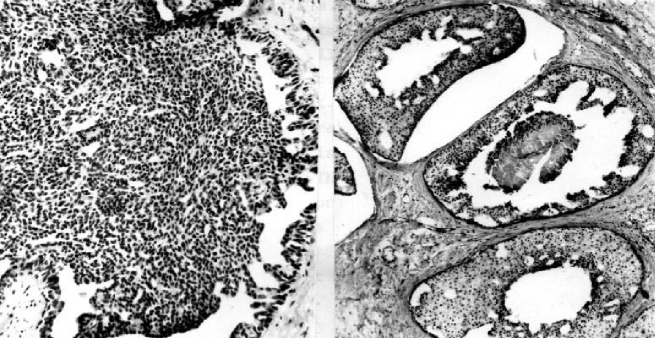

The introduction of the parameters was motivated by the fact that tumor cell shape (see Figures 6 and 7) represents a visual manifestation of an underlying balance of forces and chemical reactions [32]. Specifically, the parameters represent the following quantities:

The ability to estimate the growth pattern of an individual tumor cell type on the basis of morphological measurements should have general applicability in cellular investigations, cell–growth kinetics, cell transformation and morphogenesis [34].

Cell spreading alone is conducive to proliferation and increases in DNA synthesis, indicating that cell morphology is a critical determinant of cell function, at least in the presence of optimal growth factors and extracellular matrix (ECM) binding [35]. In many cells, the changes in morphology can stimulate cell proliferation through integrin-mediated signaling, indicating that cell shape may govern how individual cells will respond to chemical signals [36].

The proposed model (20)–(23) describes chaotic behavior relevant to the invasion of cancer cells (see Figures 5 and 6). As devices for controlling metastasis/chaos we suggest the following processes: Cellular retraining of cancer stem cells and/or activation of positive function of cyclin-dependent kinase inhibitor p27 and/or decreased expression of SATB1, which is correlated with aggressive tumor phenotype in breast cancer and shorter patient survival time [27, 29, 30, 31].